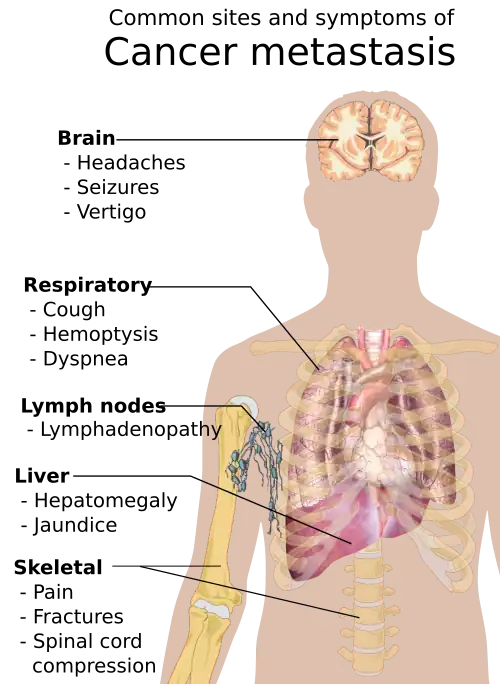

Symptoms of cancer metastasis depend on the location of the tumor.

Different types of cancers tend to metastasize to particular organs. Overall, the most common places for metastases to occur are the lungs, liver, brain, and the bones.[40]